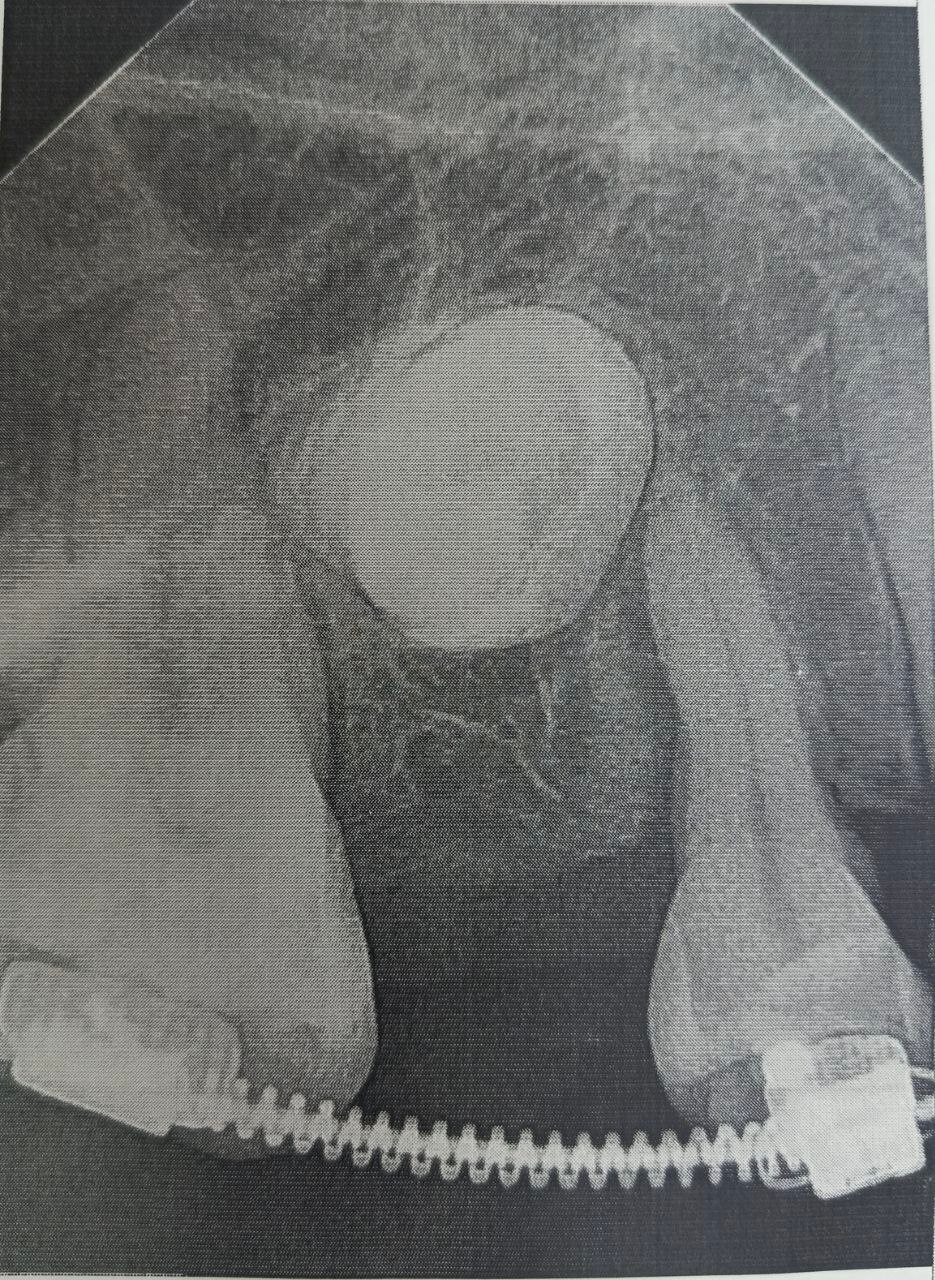

Диагностика с помощью компьютерной томографии показала сложную картину – в челюсти находились два непрорезавшихся зуба.

Когда пространство было подготовлено, хирурги провели операцию: раскрыли десну, чтобы обнажить коронки непрорезавшихся зубов, и зафиксировали на них специальные ортодонтические кнопки.